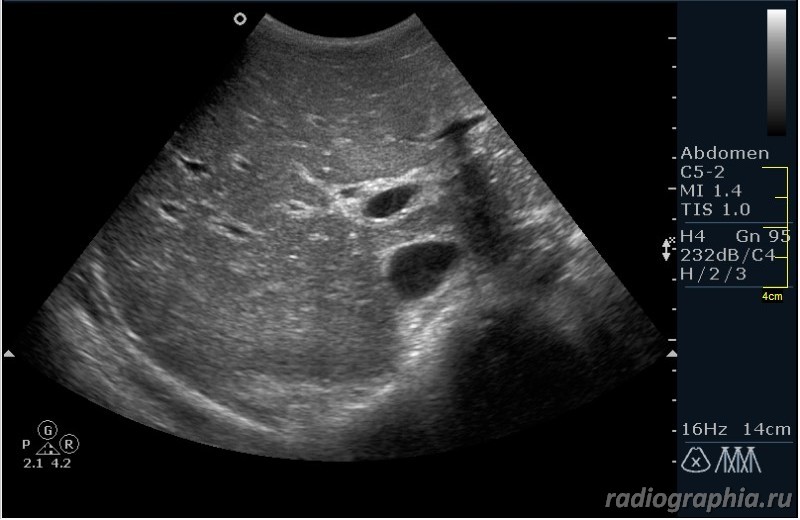

Как вы думаете, при какой патологии можно наблюдать такую сонографическую картину?

Похоже на расширенные внутрипеченочные протоки ,отек стенок ж.пузыря--может быть при остром гепатите

склерозирующий холангит? Насколько я помню, протоки при СХ выглядят как "четки"

Гепатиты - такой ответ автор считает верным.